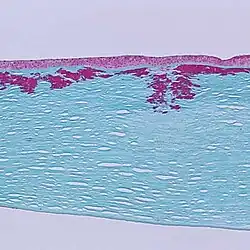

Дистрофия боуменовой мембраны I типа, более известная как дистрофия роговицы Рейса — Бюклерса — редкая форма дистрофии роговой оболочки глаза человека, поражающая слой под названием боуменова мембрана. Болезнь ассоциирована с мутациями гена TGFBI, кодирующего кератоэпителин.

Симметричные ретикулярные помутнения, обычно возникающие в роговице обоих глаз к 4—5 годам, приводят к выпуклостям эпителия роговицы, вызывая эрозии, провоцируя приступы гиперемии, боли, светобоязни.